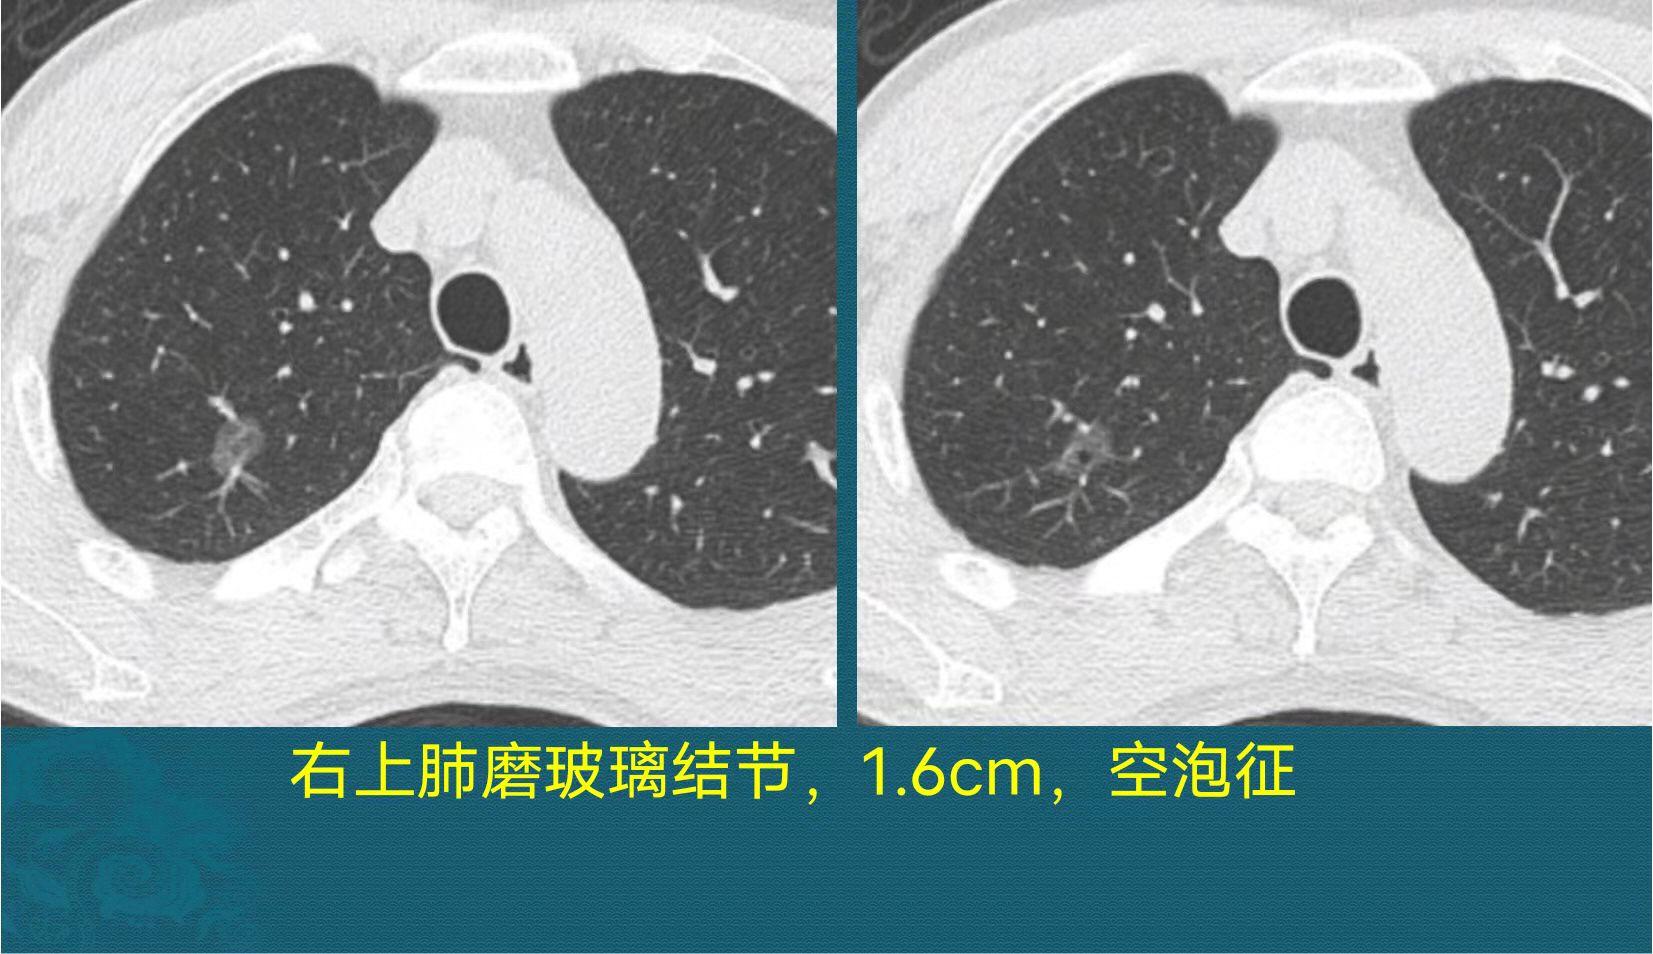

先看一个治愈的肺癌病例,这种类型不会复发,手术可以治愈:

这是一位65岁男子,咳嗽3天,胸部CT发现磨玻璃肺结节,长径1.6cm,里面有个黑色小空泡征,短期复查结节没有吸收,就做了胸腔镜微创手术,病理是微浸润肺腺癌。

肺腺癌的发展分3个阶段,依次是:浸润前病变(包括不典型增生和原位腺癌)、微浸润腺癌、浸润性腺癌。其中浸润前病变首选定期复查,很多人可以几十年不进展,而微浸润腺癌可以手术治愈,且不会转移,手术后不复发,也不需要后续治疗,术后定期复查一下即可。上图这位老爷子就属于这种情况。